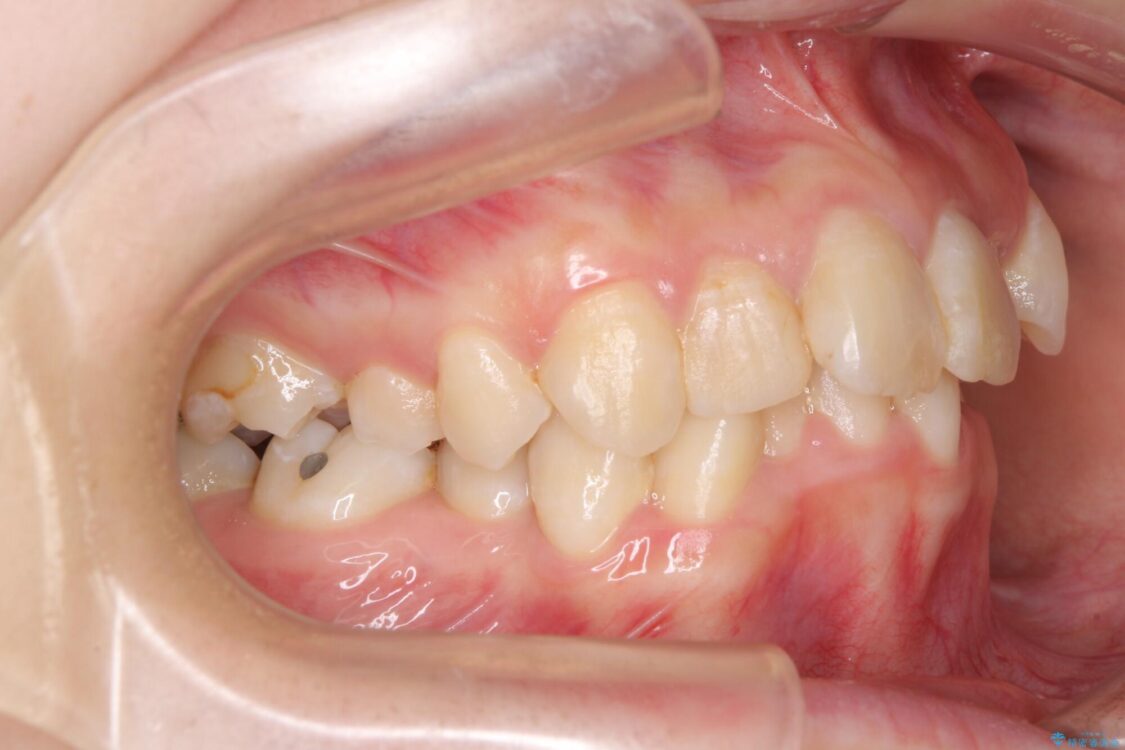

内側に倒れ込んだ歯や下の前歯が隠れてしまうほどの咬み合わせを改善したいとのことで来院された患者様です。

下顎の叢生を解消するために抜歯が必要であり、奥歯の咬み合わせや口元の印象から、上顎も同様に抜歯と判断し、上下左右の第1小臼歯4本抜歯してワイヤー装置にて矯正治療を行うこととしました。

治療前

• デコボコと深い咬み合わせ ワイヤー装置での抜歯矯正 治療前画像